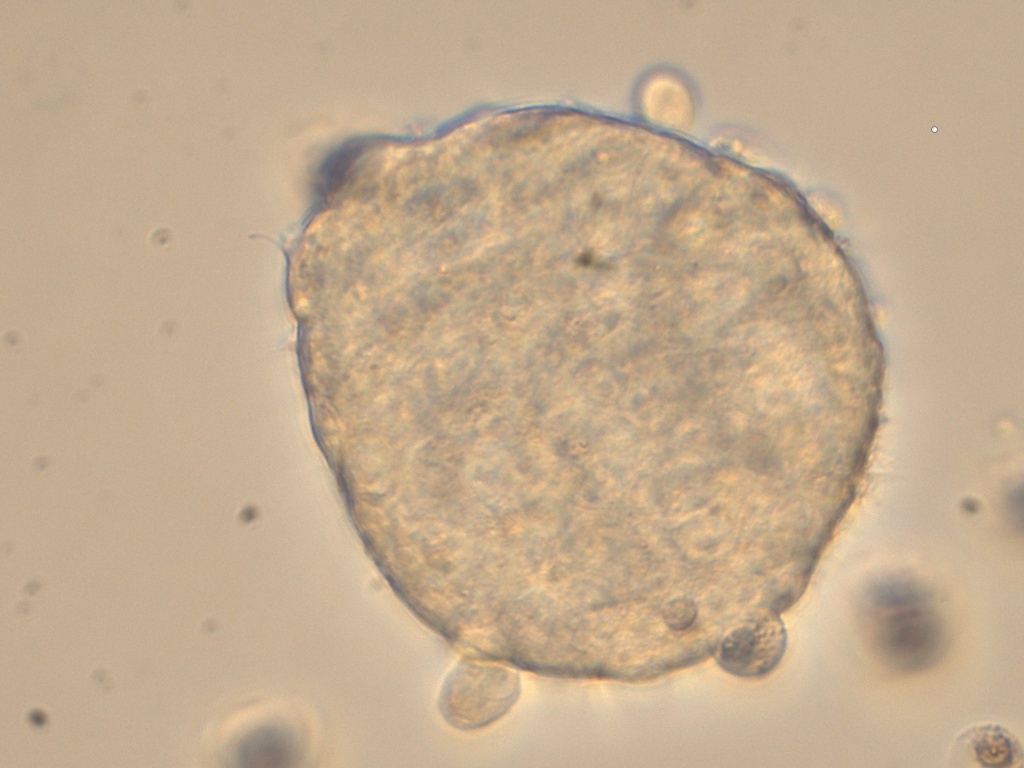

Cancer Stem cells Spheres Medium(肿瘤干细胞成球培养基)是一款用于将癌症干细胞(CSC)培养成3D球的培养基���。癌症干细胞(CSC)被定义为肿瘤内的一小部分细胞���,具有自我更新的能力����,并且经常在化学疗法治疗后驱动肿瘤的进展和复发����。因此����,针对CSC的特定疗法的开发有望改善癌症患者的生存和生活质量���,特别是对于患有转移性疾病的患者�����。

肿瘤干细胞成球培养基是一种新的化学成分确定和无血清的癌症干细胞培养基�����,可支持CSC形成3D球状细胞的聚集和扩增�����。

7、 4-10 天左右在超低吸附板孔中央区域会形成肿瘤球体;